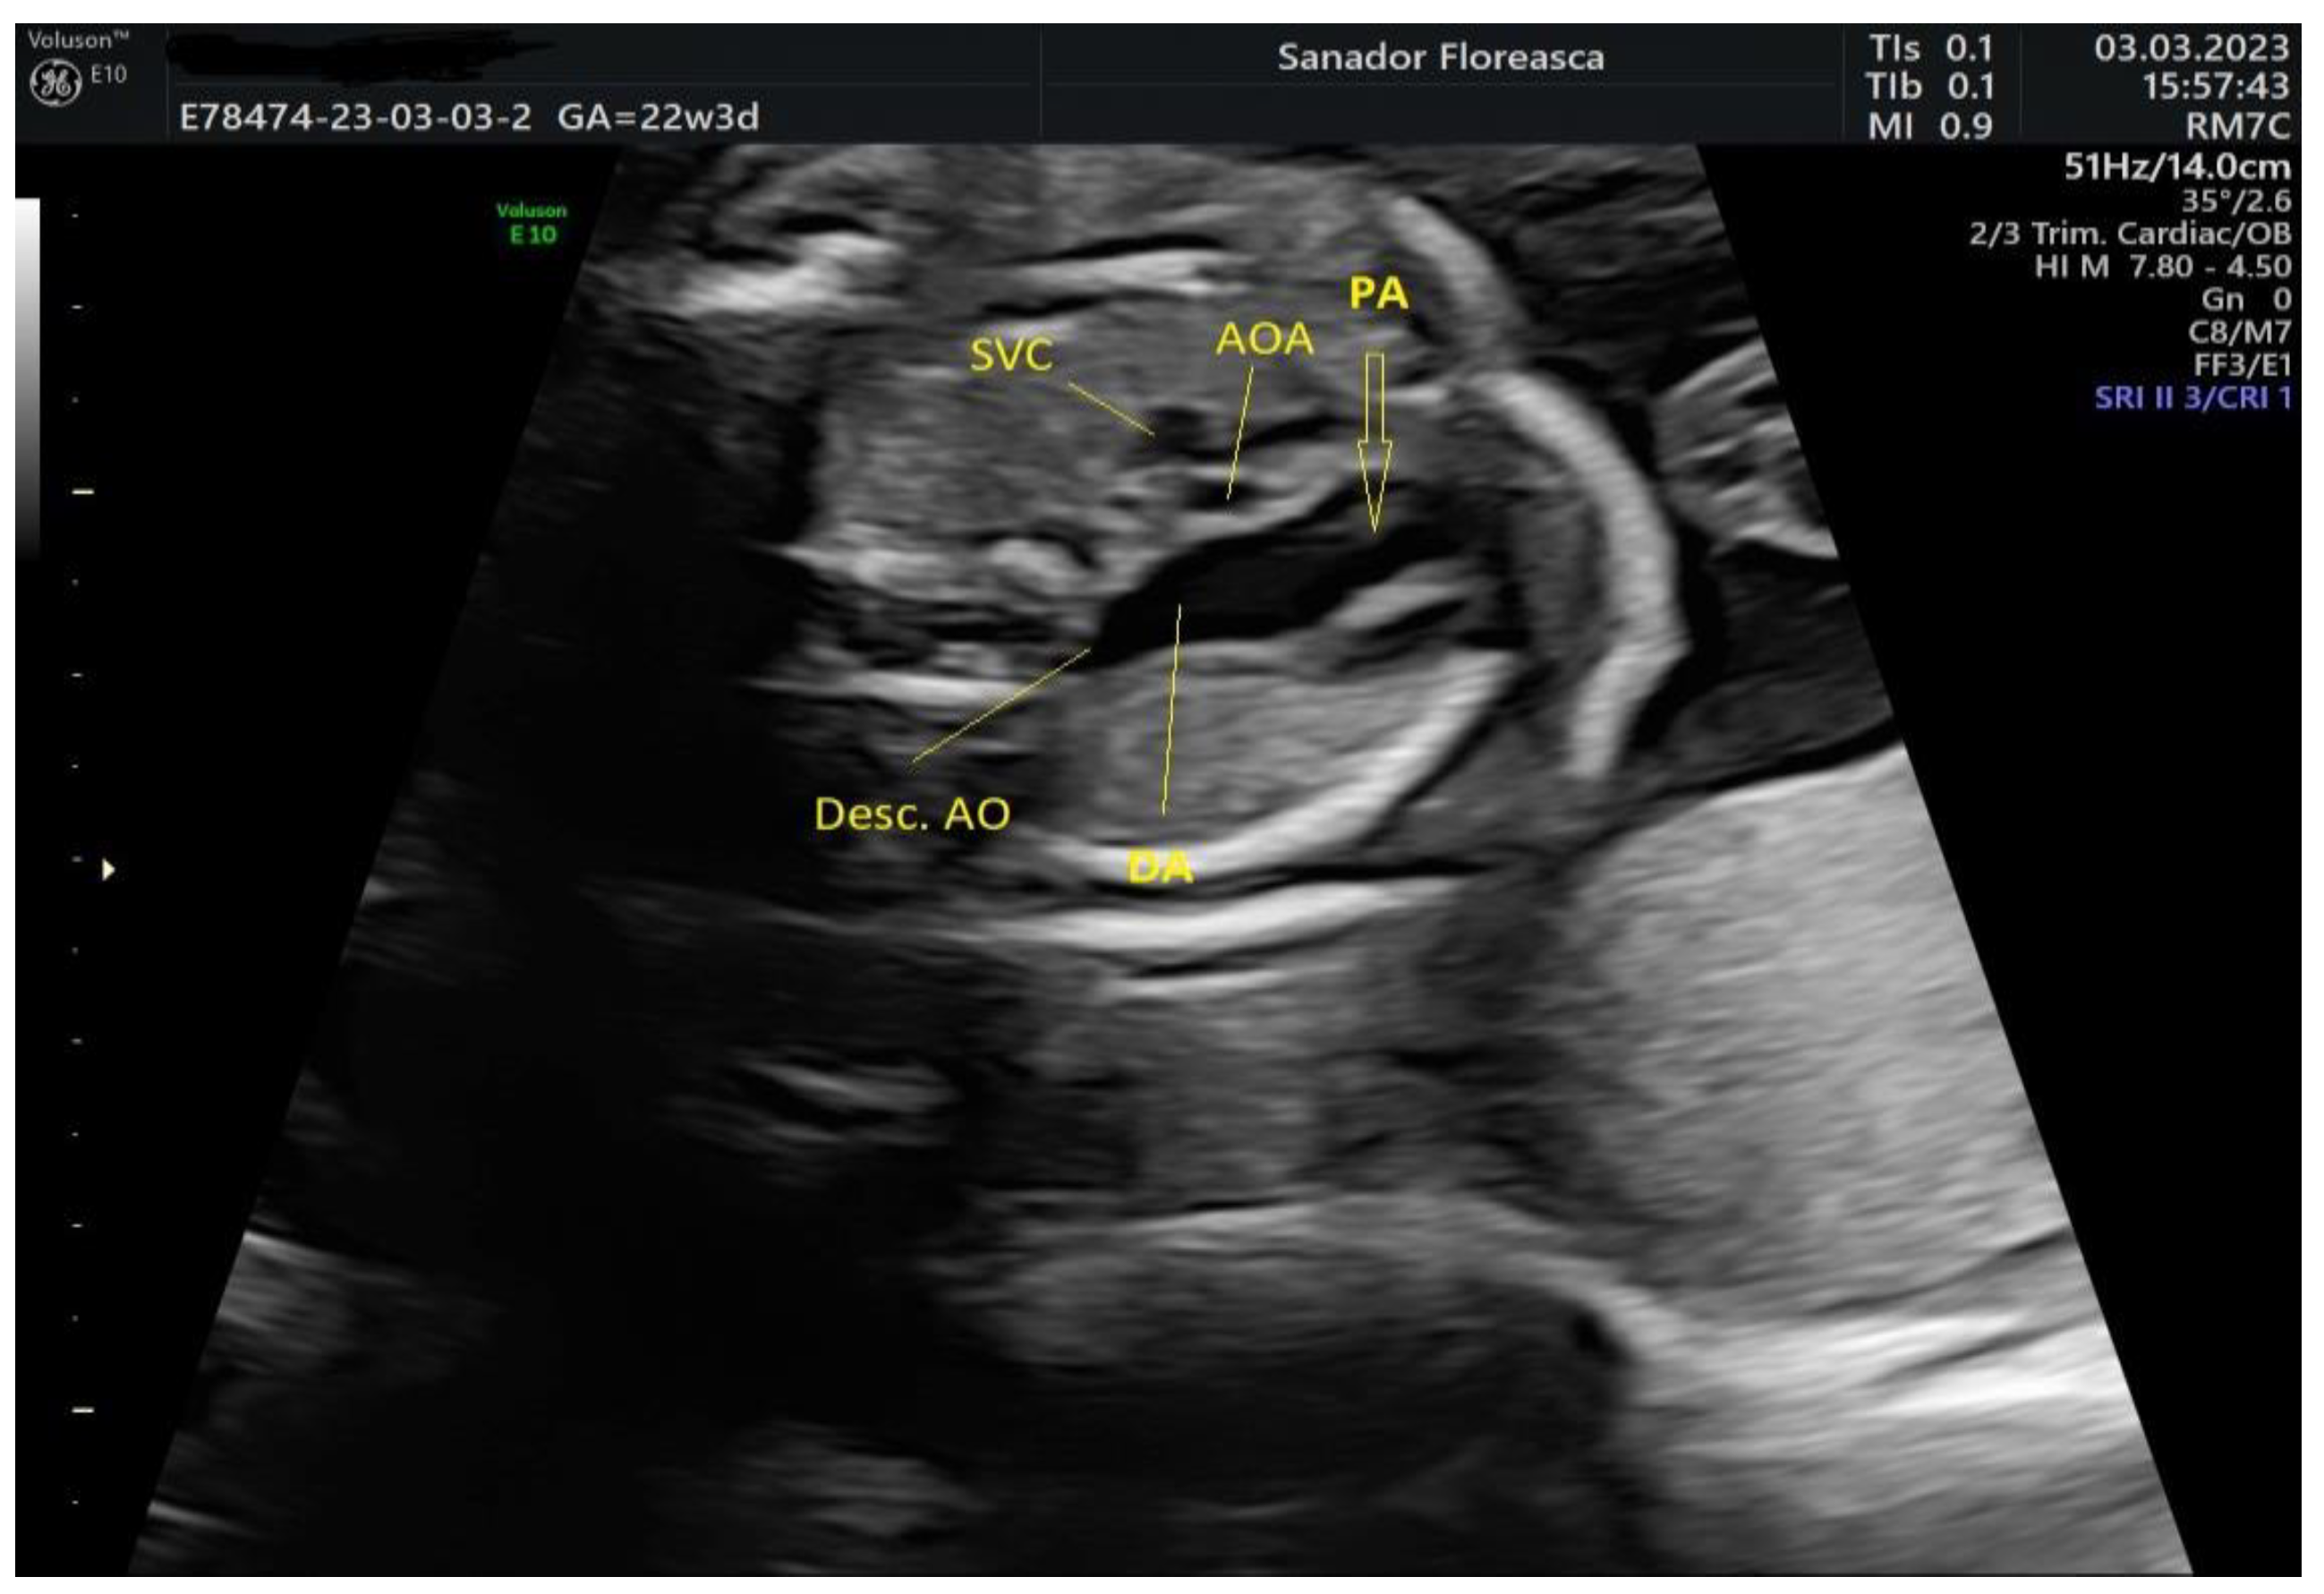

Cardiologic diagnosis | IAA type B, malalignment-type VSD, pulmonary valve dyplasia, ARSA |

Other ultrasonographic findings | Polyhydramnios Enlarged CSP Thymus hypoplasia Bulbous nose |